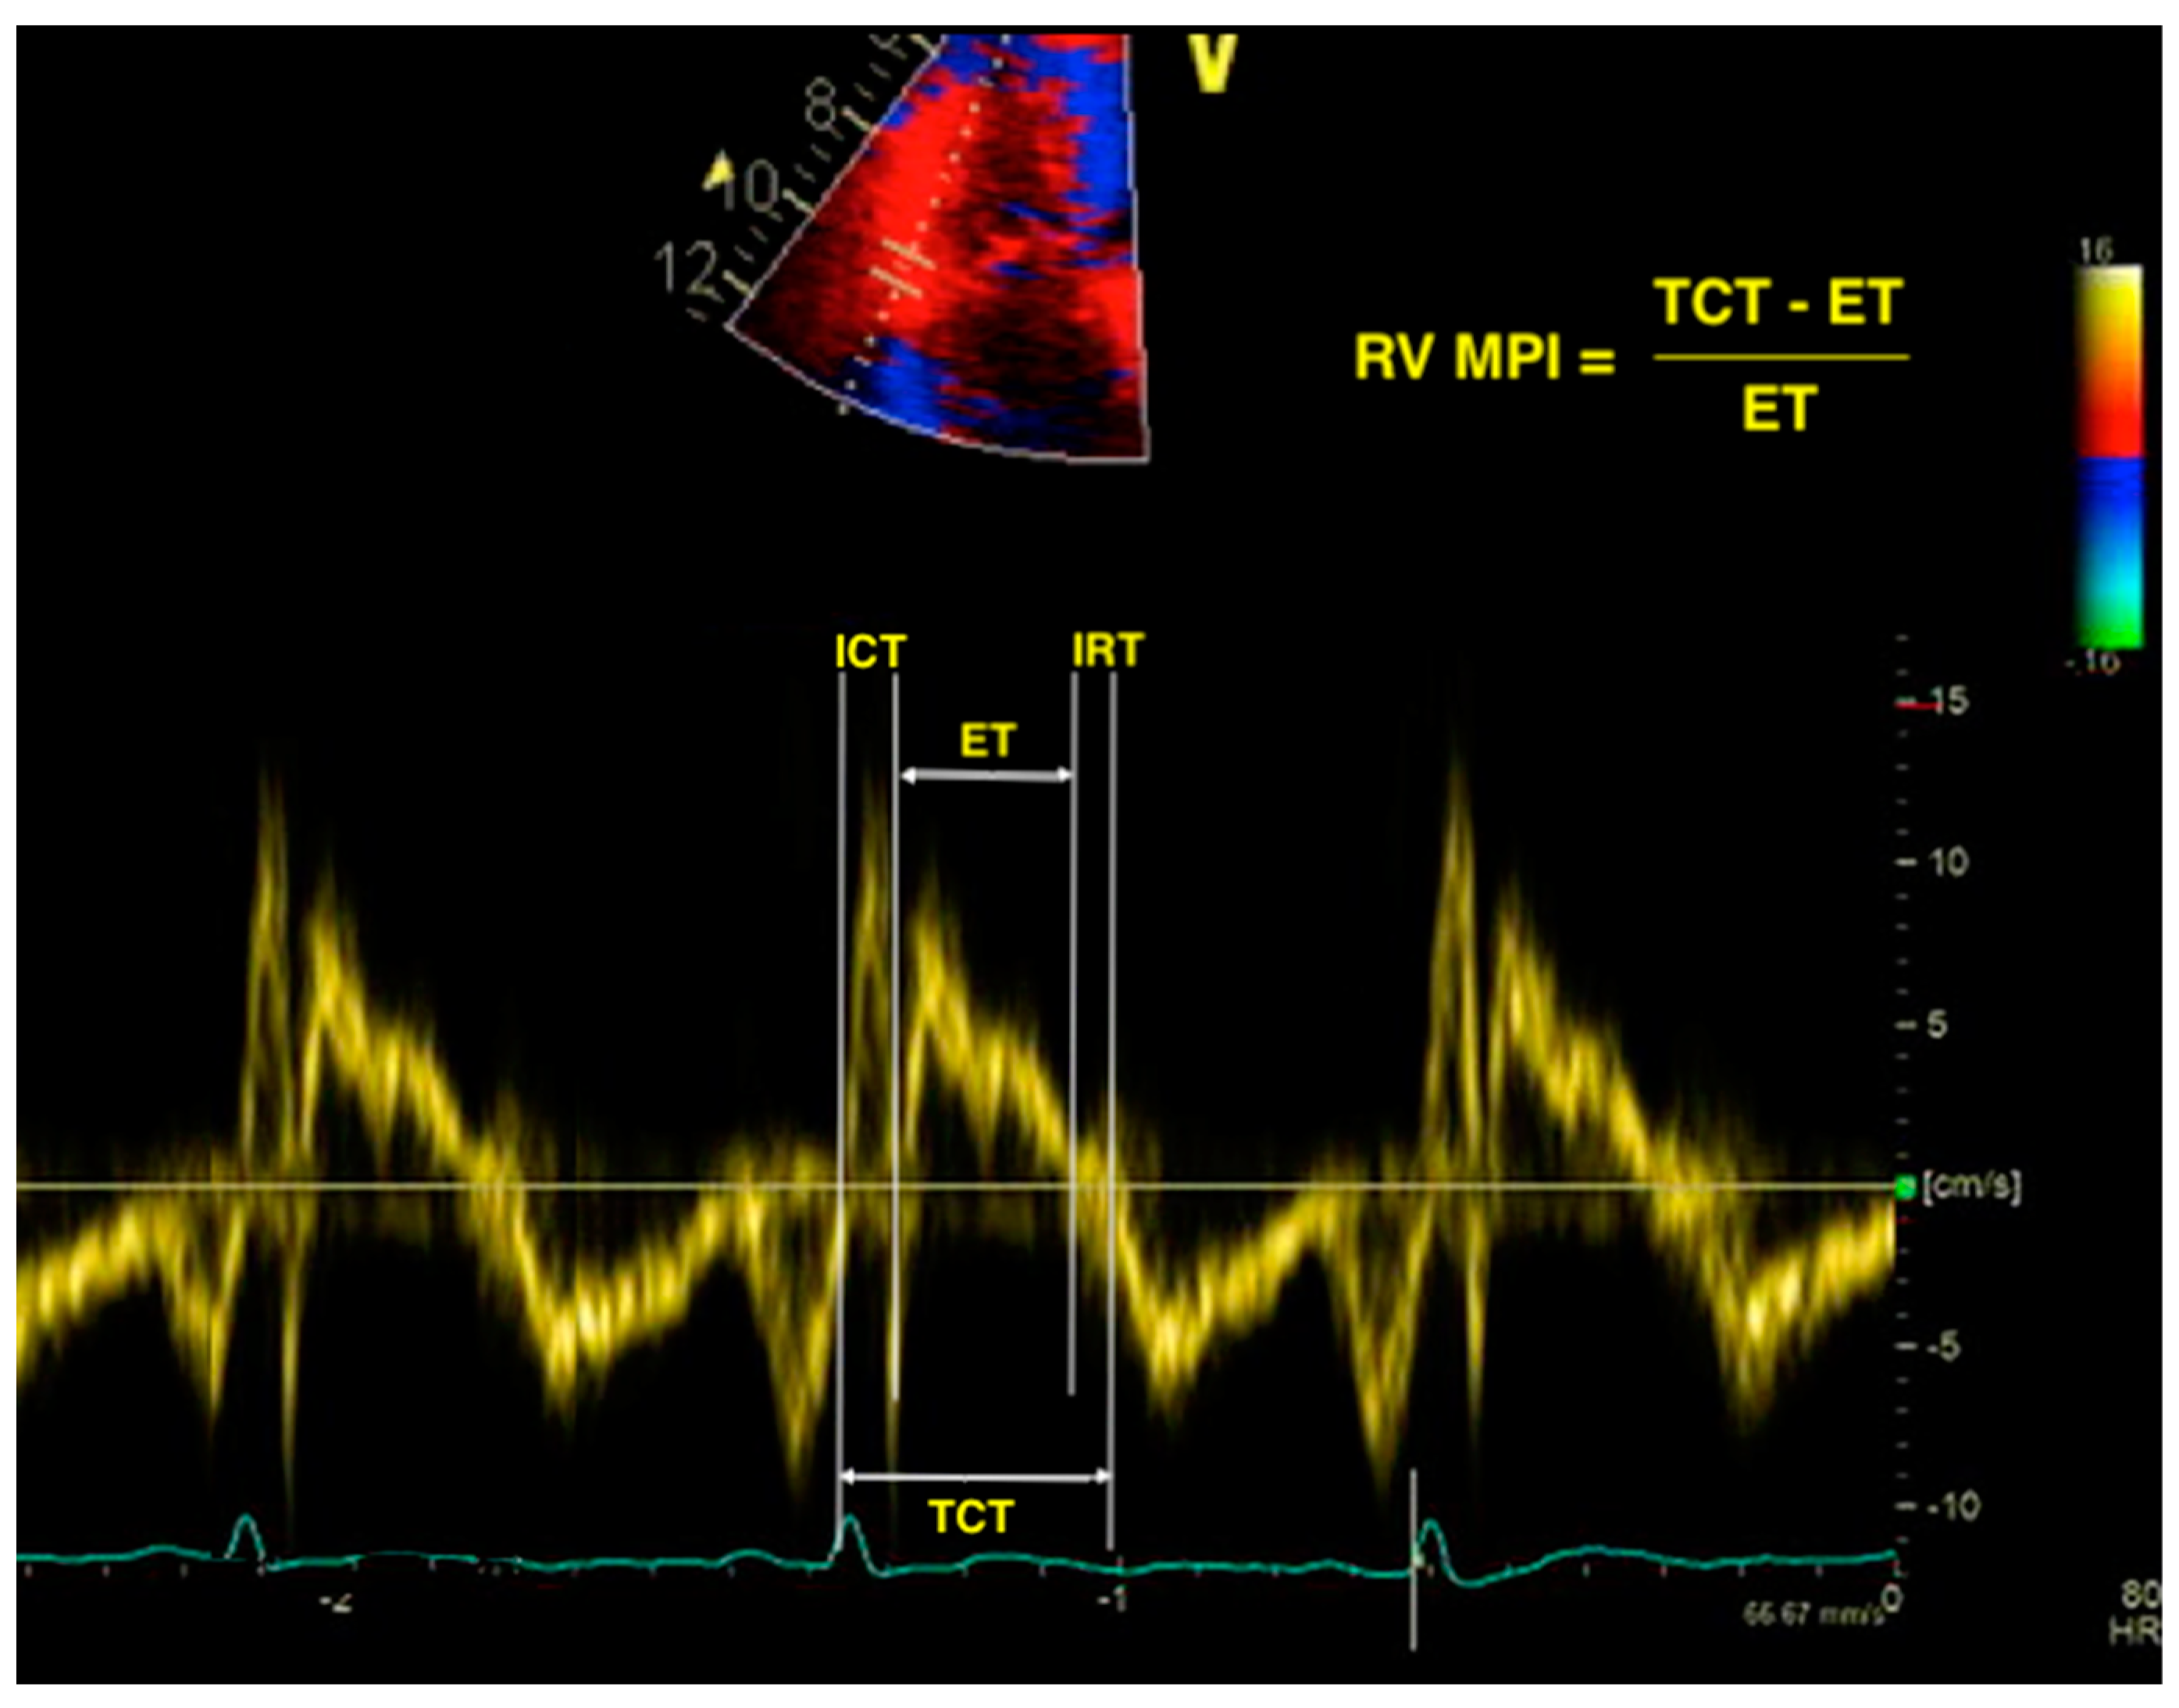

The RV myocardial performance index, also known as the right Tei index, is a measure of both systolic and diastolic RV function. It is a unitless parameter, calculated by dividing the total isovolumic time (isovolumic contraction plus isovolumic relaxation) by the ejection time (ET) [30]. Systolic dysfunction prolongs the isovolumic contraction time (ICT) and shortens the ET, while prolonged isovolumic relaxation time (IRT) is encountered in both systolic and diastolic dysfunction. Therefore, impaired RV global function will lead to a high RV MPI. The parameter can be measured using either pulsed-wave Doppler or tissue Doppler (Figure 1). The proposed cutoff values for abnormal RV MPI are >0.43 using pulsed Doppler and >0.54 using tissue Doppler [26]. The advantage of RV MPI is that it bypasses the limitations of the complex RV geometry, as it is only derived from time intervals and makes use of no assumption of RV shape. However, it is unreliable in patients with elevated right atrial pressure, and irregular rhythms make MPI difficult to calculate [29,30].

Figure 1.

Calculation of right ventricular myocardial performance index (RV MPI) using the tissue Doppler imaging (TDI) method. RV—right ventricle; MPI—myocardial performance index; TDI—tissue Doppler imaging; ICT—isovolumic contraction time; ET—ejection time; IRT—isovolumic relaxation time; TCT—total contraction time.